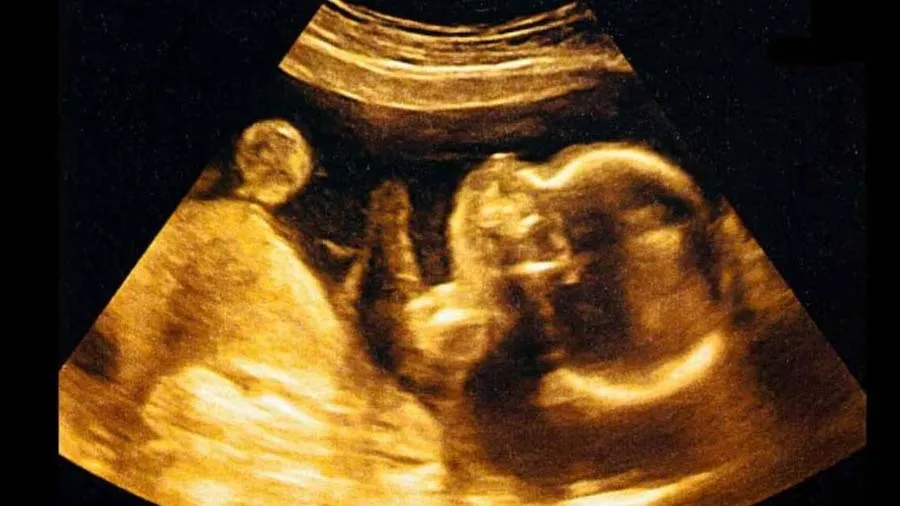

મેડિકલ સાયન્સના ઇતિહાસમાં એ પહેલી વખત થયું છે કે, ડૉક્ટરોએ ગર્ભમાં ઉછરી રહેલા ભ્રૂણની સર્જરી કરી હોય. આ સર્જરી પૂરી રીતે સફળ રહી. એમ કરીને ડૉક્ટર્સે બાળકના વિકસિત થઈ રહેલા મસ્તિષ્કમાં ઉછરી રહેલા ઘાતક ડિસઓર્ડરને દૂર કરી દીધો છે. સ્ટ્રોકમાં પ્રકાશિત શોધ મુજબ, આ સર્જરી માટે અલ્ટ્રાસાઉન્ડનો ઉપયોગ કરવામાં આવ્યો. ભ્રૂણનું ઓપરેશન ગર્ભાવસ્થાના 34માં અઠવાડિયામાં કરવામાં આવ્યું. ભ્રૂણમાં ગેલેન મેલાફોર્મેશનની જાણકારી મળી હતી, જે મોટા ભાગે ઘાતક અને આક્રમક હોય છે.

ગર્ભાવસ્થા દરમિયાન તેની સારવાર કરવામાં આવે છે અને સામાન્ય રીતે ઓડોવસ્કુલર એમ્બોલાઇઝેશન નામની પ્રક્રિયા દ્વારા સારવાર કરવામાં આવે છે. સર્જાનોએ આ પ્રકારની સર્જરી પહેલા પણ કરી હતી, પરંતુ એ પહેલી વખત હતું કે તેને પૂરી રીતે ગર્ભાશયમાં કરવામાં આવ્યું હતું. US ફૂડ એન્ડ ડ્રગ એડમિનિસ્ટ્રેશનની દેખરેખમાં, તેઓ ભ્રૂણના મસ્તિષ્કમાં ઉચ્ચ દબાવવાળા બ્લડ વેસલ્સને બ્લોક કરવામાં સફળ રહ્યા, જેથી જન્મ દરમિયાન દબાવ વધારા રોકી શકાય.